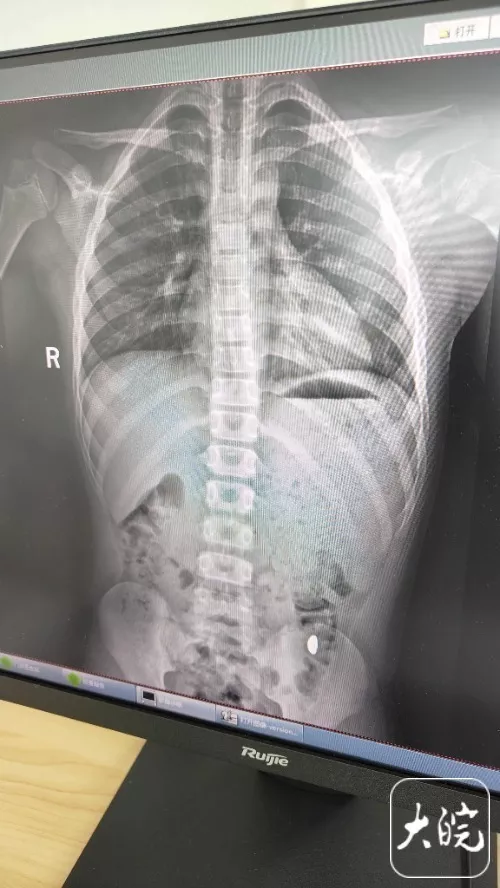

昆山市第五人民医院门诊病历单显示,医生在现病史一栏写着,患儿5天前误吞约10克黄金,期间解2次大便未发现,目前无腹痛、呕吐等症状,诊断结果显示胃内有异物。

右下加亮点为金豆。